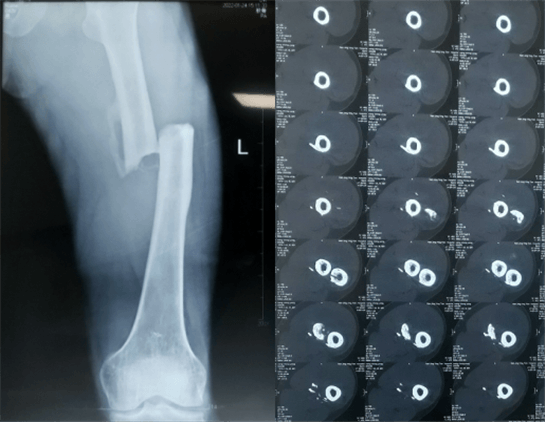

患者:男性,43歲,左股骨干骨折髓內(nèi)釘內(nèi)固定術(shù)

醫(yī)院:南京應(yīng)天骨科醫(yī)院

股骨是下肢的主要負(fù)重骨,有其特殊的解剖關(guān)系,周圍肌肉發(fā)達(dá),因此一旦股骨干骨折后如果治療不當(dāng),容易造成肌肉牽拉,導(dǎo)致畸形和功能障礙。治療股骨干骨折,必須遵循恢復(fù)肢體的長度及力線,無旋轉(zhuǎn),盡量行以微創(chuàng),保護(hù)骨折局部血運(yùn),促進(jìn)愈合。髓內(nèi)釘對(duì)骨折的固定能夠達(dá)到較大的穩(wěn)定性和堅(jiān)固性,可以減少醫(yī)源性污染,減少軟組織分離及周圍血供破壞,有利于骨折早期愈合,是治療股骨干骨折的首要治療方法。

術(shù)前檢查